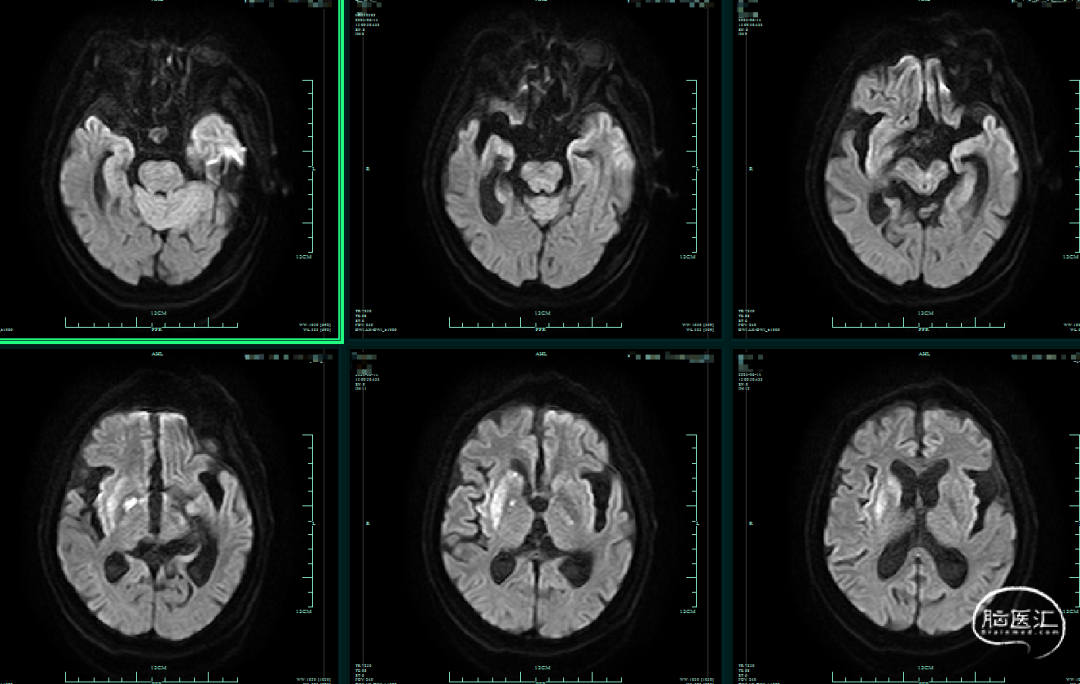

➤术后影像

术后第一天,头颅DWI可见尾状核及基底节区新发脑梗死;MRA可见右侧颈内动脉、右侧大脑中动脉、双侧大脑前动脉无再次闭塞。